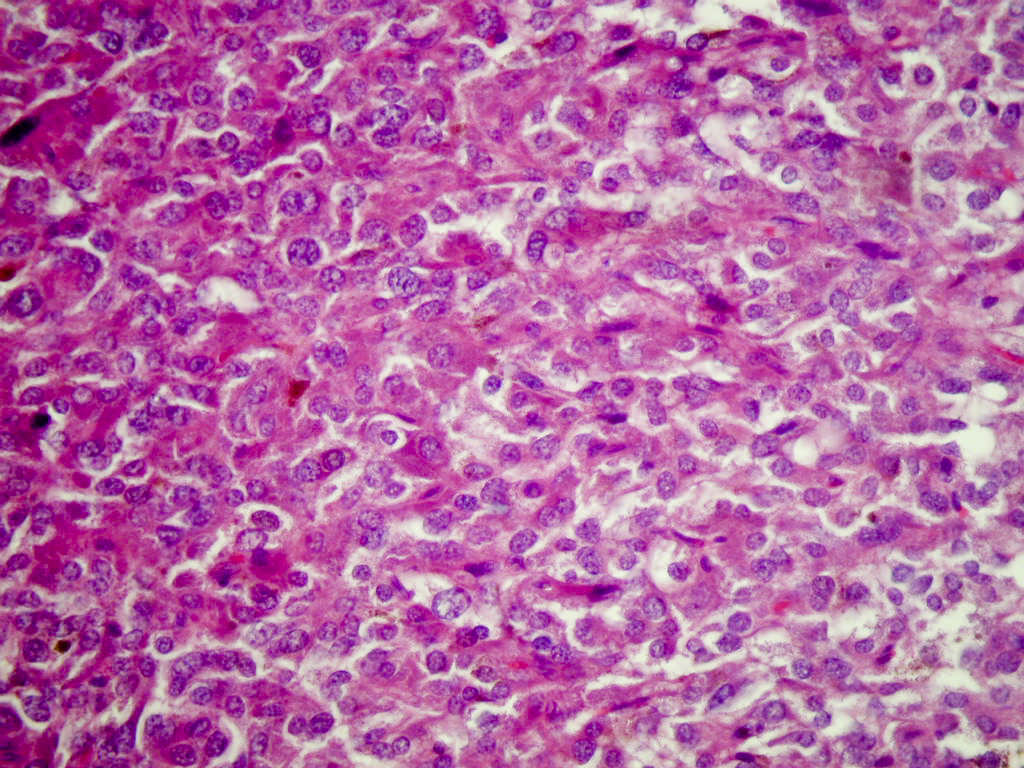

- Typical morphology: epithelioid cells with abundant, eosinophilic / amphophilic, granular cytoplasm and round / ovoid, vesicular / salt and pepper nuclei, arranged in a nested / zellballen pattern and separated by fibrovascular septae with sustentacular cells (Am J Surg Pathol 2004;28:94, World J Clin Cases 2014;2:591, Endocr Pathol 2022;33:90)

- May have focal pleomorphism, nuclear hyperchromasia, low mitotic activity or clear cytoplasm

Contributed by Theodorus H. van der Kwast, M.D., Ph.D., Michelle R. Downes, M.D., Debra L. Zynger, M.D. and David Cohen, M.B.B.Ch., M.D.

- Microscopic description: This specimen shows an unencapsulated, monomorphous population of round tumor cells in a nested / zellballen pattern with delicate vascular septa and intervening extravasated red blood cells. It predominantly involves the lamina propria of the bladder but in 1 tissue piece clearly involves muscularis propria. The tumor cells have abundant amphophilic cytoplasm and vesicular chromatin with occasional small nucleoli. There is no necrosis, diffuse growth pattern or vascular space invasion identified. The mitotic count is (maximally) 1/10 high power fields. Immunohistochemistry shows the tumor cells to be positive for GATA3 with strong and diffuse expression of synaptophysin and chromogranin, as well as retention of SDHB staining. The tumor cells are negative for AE1 / AE3, HMWK and p63. The Ki67 proliferation index is < 1%. S100 shows faint nuclear and cytoplasmic staining with occasional sustentacular cells identified.

- Microscopic description: Sections show unremarkable surface urothelium with a lesion in the deep lamina propria comprised of large eosinophilic cells with hyperchromatic, focally enlarged nuclei with occasional intranuclear inclusions. A fine vascular plexus is identified in some areas. Necrosis and hemorrhage are not identified. Mitotic rate = 1/10 high power fields (field of view [FOV] = 0.55 mm). The lesion extends to the cauterized base of the specimen. Immunostains confirm the lesion expresses synaptophysin, chromogranin and GATA3. SDHB is retained. AE1 / AE3, CD45, p63 and NKX3.1 are negative.